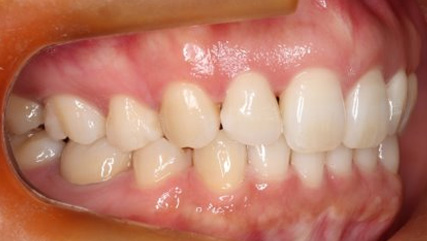

上顎前突といわれ、上顎の前歯が唇側に出ている状態を言います。

前歯が出ることで見た目の問題もありますが、口を閉じることができない、口呼吸をしてしまう、外傷などのリスクがあります。

日本人に叢生の次に多い不正咬合と言われており、自然に治ることはありません。また上の前歯が出ている事だけが気になるかもしれませんが、多くの場合、上顎の奥歯の位置に問題があることが多く、部分矯正でなく根本的な治療をした方がいい場合が殆どです。

口を閉じることができないことで、鼻呼吸でなく口呼吸をしてしまい、結果、成長期の場合顎の骨の成長を邪魔してしまうとも言われております。その他、口呼吸はアトピーなどを含むアレルギー症状の悪化、風邪を含むウイルス性の感染症にかかりやすいなどのリスクも増大してしまいます。

歯並びだけでなく全身への影響も多い為、早期の治療をおすすめ致します。